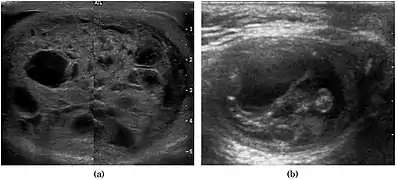

Fig. 6. Mature cystic teratoma. (a) Composite Image. Mature cystic teratoma in a 29-year-old man. Longitudinal sonography image of the right testis shows a multilocular cystic mass. (b) Mature cystic teratoma in a 6-year-old boy. Longitudinal sonography of the right testis shows a cystic mass containing calcification with no obvious acoustic shadow.